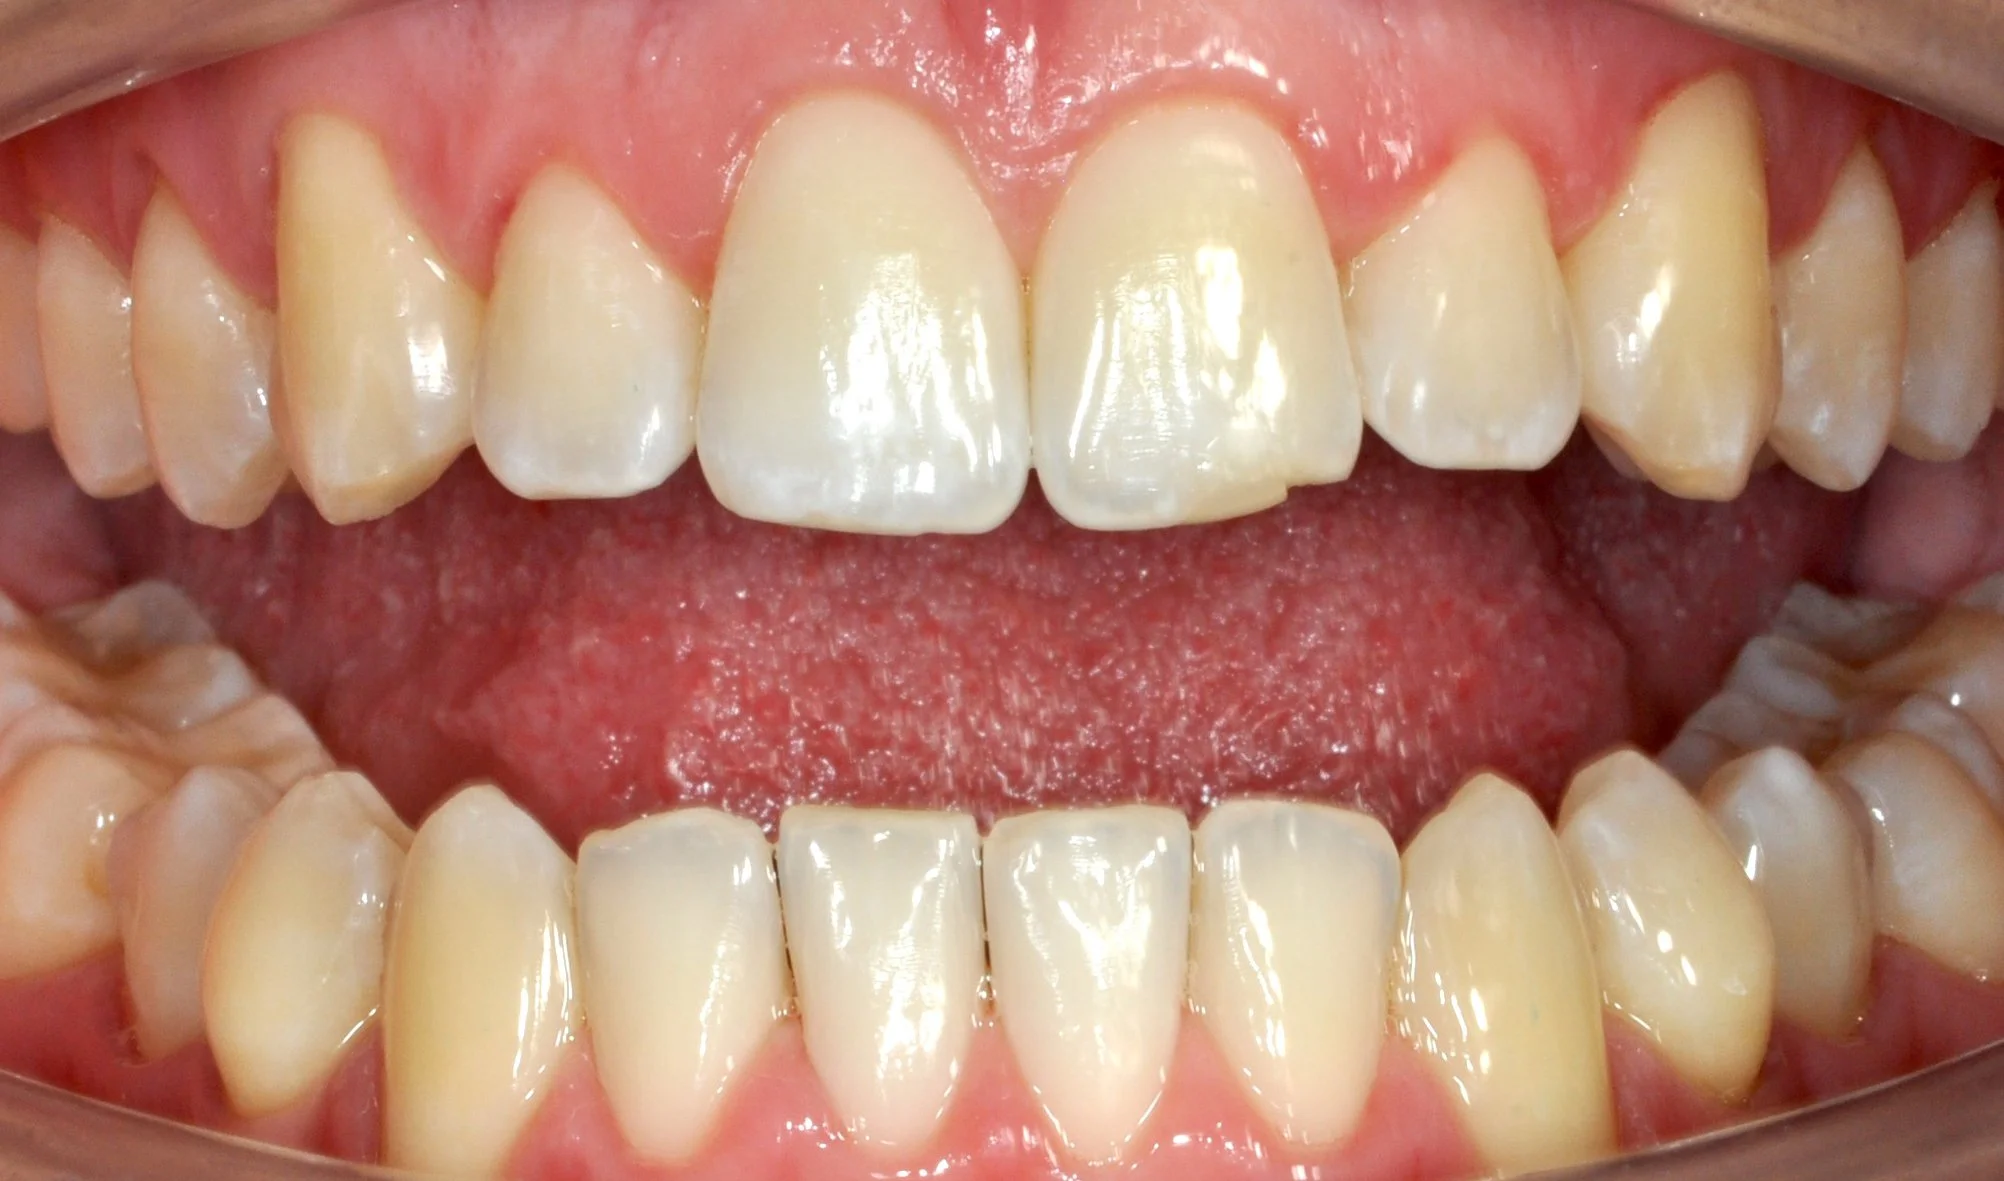

Giovane paziente in fase di crescita con denti superiori troppo in avanti rispetto agli inferiori, arcate strette e rotazioni importanti di alcuni elementi.

Grazie al trattamento con allineatori trasparenti, in 18 mesi è stato possibile accompagnare la crescita, correggere l’allineamento dei denti e migliorare il rapporto tra le arcate, ottenendo un sorriso più armonioso e funzionale.

PRIMA